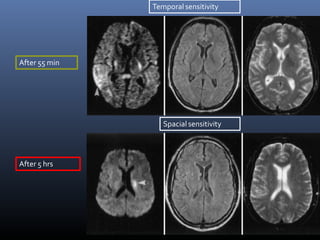

Conventional MRI in acute

stroke- T2 and FLAIR

• These sequences detect 80%

infarct before 24 hrs

• It can be negative upto 2 to 4

hrs

Temporal sensitivity

Spacial sensitivity

After 55 min

After 5 hrs